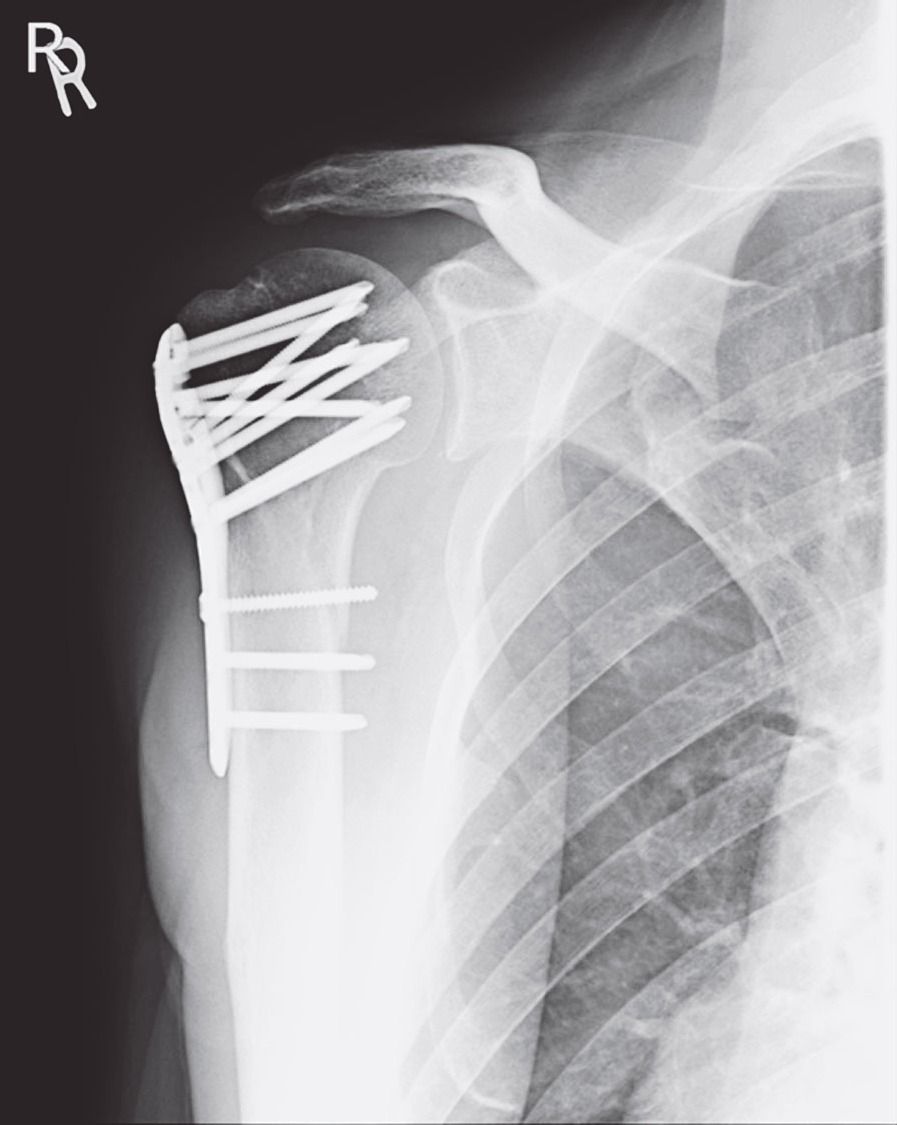

連載「交通安全・医理工連携の今 『世界一』への挑戦」(97)黒住健人 交通事故と外傷(1)外傷と骨折、骨折の機序、治療の概要